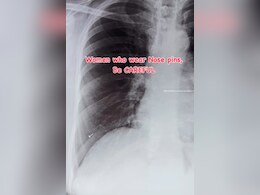

सांस के साथ फेफड़ों तक चली गई नोज़ पिन, एक्स-रे देख डॉक्टर के उड़े होश, मसां-मसां बची जान

Nose Pin In Lungs: कुछ समय पहले एक मामला सामने आया. जिसमें एक महिला के फेफड़ों में एक नोजपिन मिली. बता दें कि इस तरह से मामले आपके लिए खतरनाक साबित हो सकते हैं.